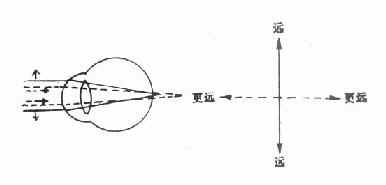

散光眼分规则与不规则两类,一般屈光学上所说的散光眼都是指前者。(图16-8)

图16-8 史氏光锥

VV′代表垂直子午线,其弯曲度大,焦距短,先成焦点。HH′代表水平子午线,其弯曲度小,焦距长,后成焦点。视网膜位于史氏光锥的A.B.C.D.E.F处时,可形成如下几种规则散光:A:复性远视散光B:单纯远视散光 C、D:混合性散光 E:单纯近视散光 F:复性近视散光